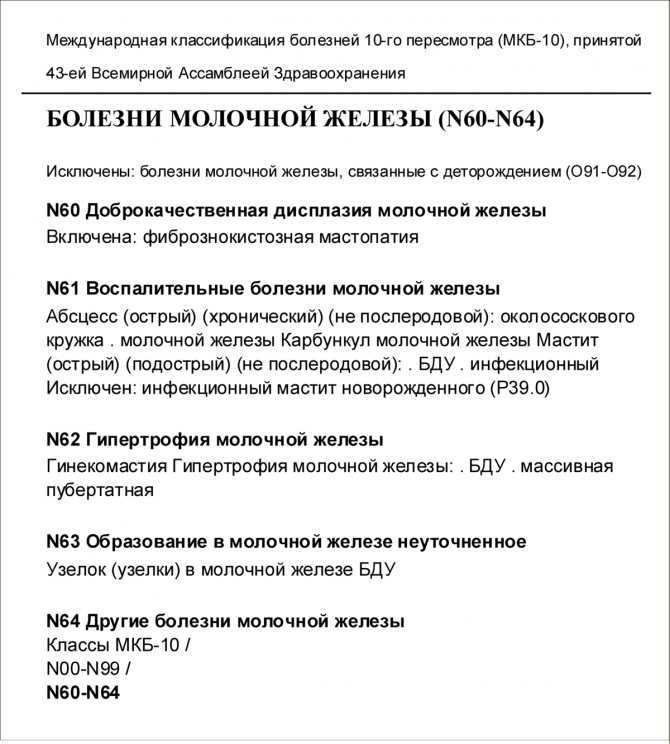

Код мкб 10 атерома головы

Код мкб 10 атерома головы 109 фото